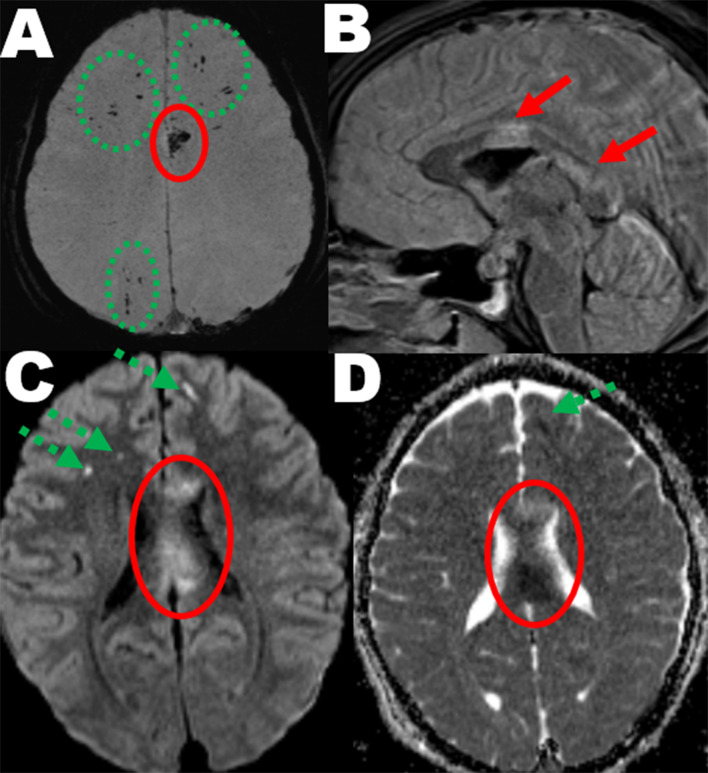

Moderate and severe traumatic brain injury: abbreviated injury scale scoring and coding of traumatic axonal injury from early MRI.